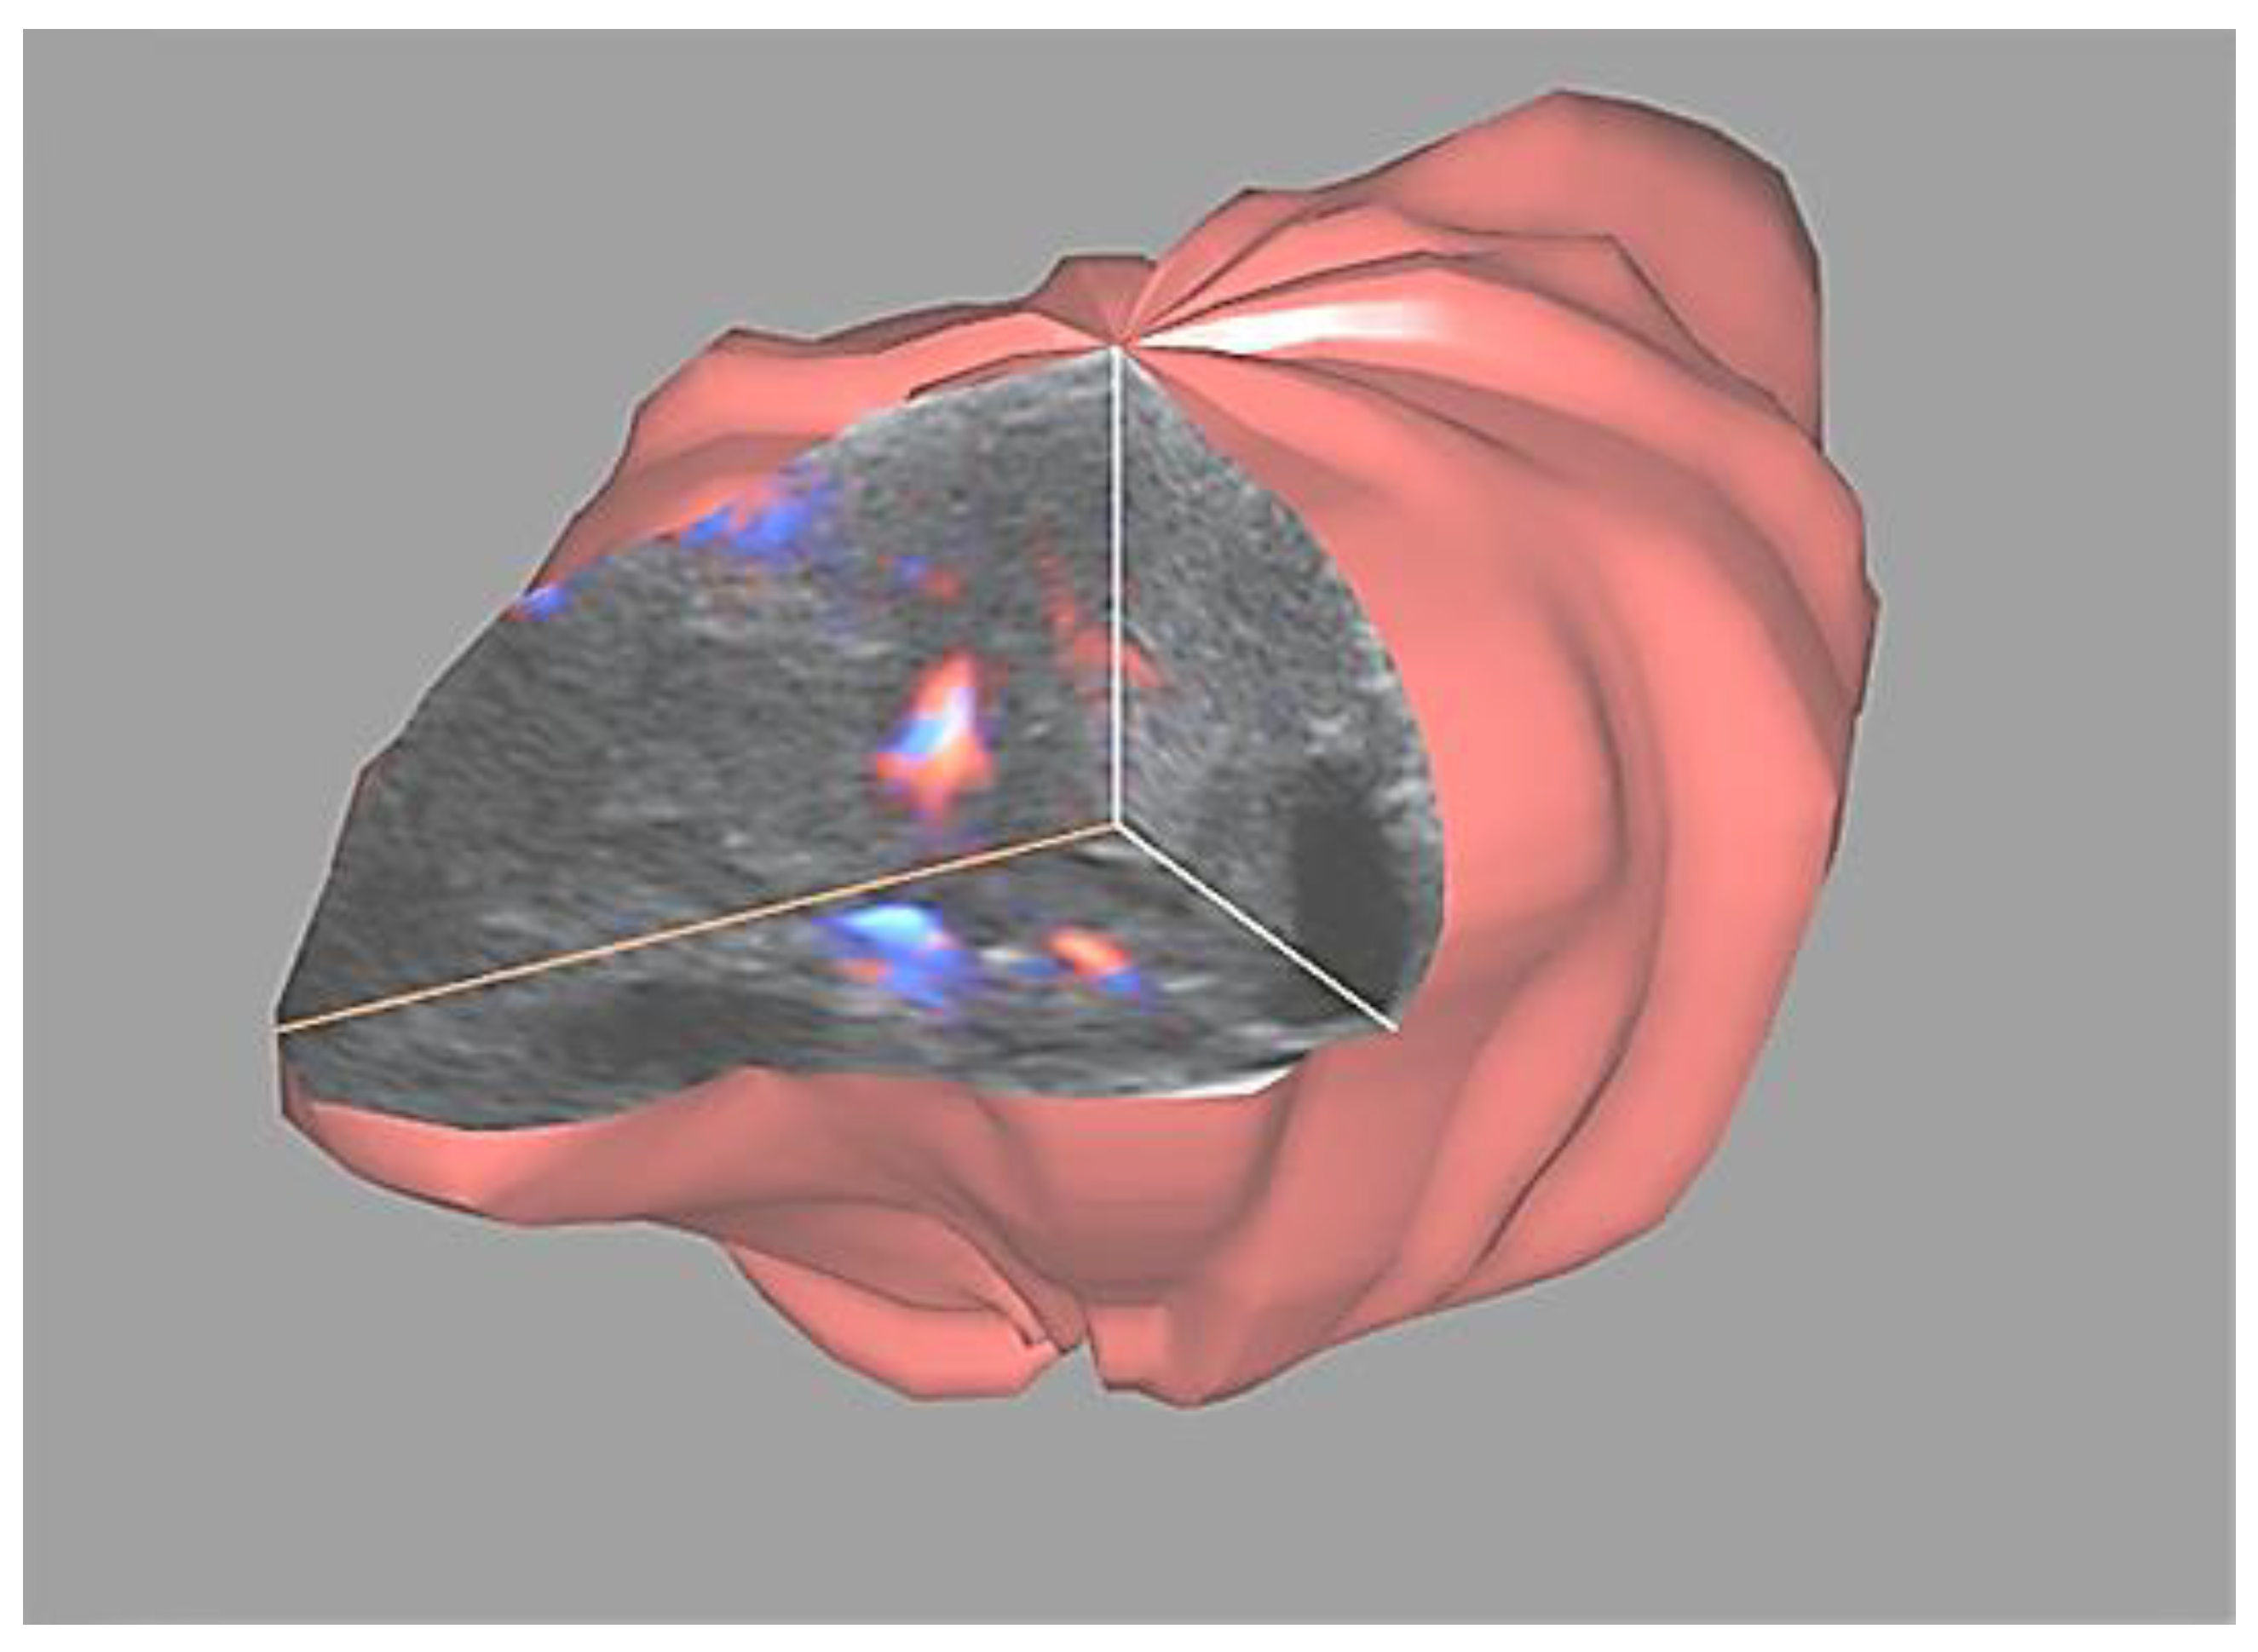

4D Doppler Ultrasound in High Grade Serous Ovarian Cancer Vascularity Evaluation—Preliminary Study